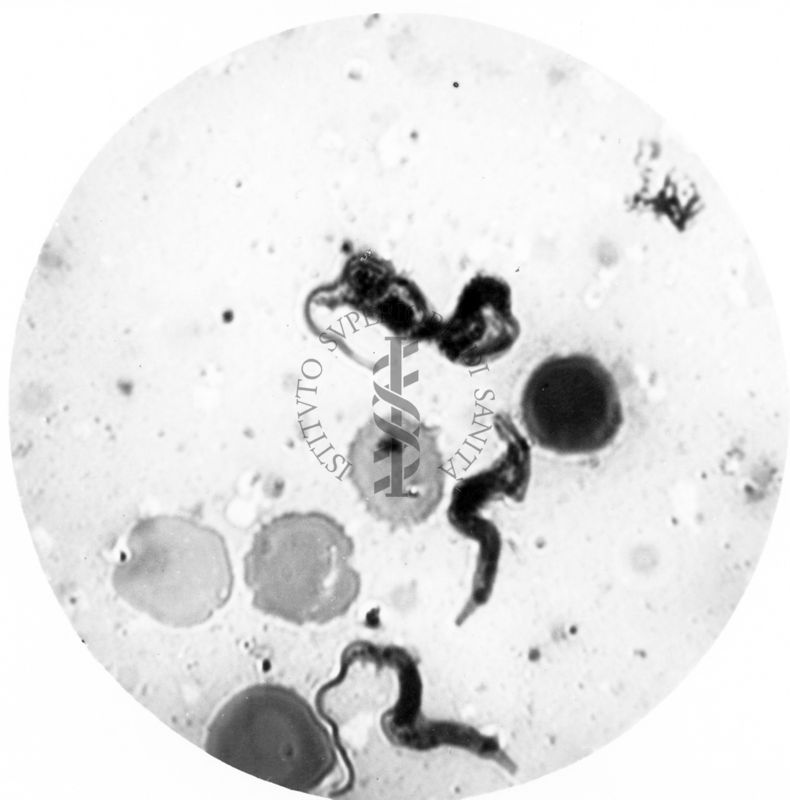

Trypanosoma gambiense - forma tipo A e tipo B in propabile singamia

Roma, 1934